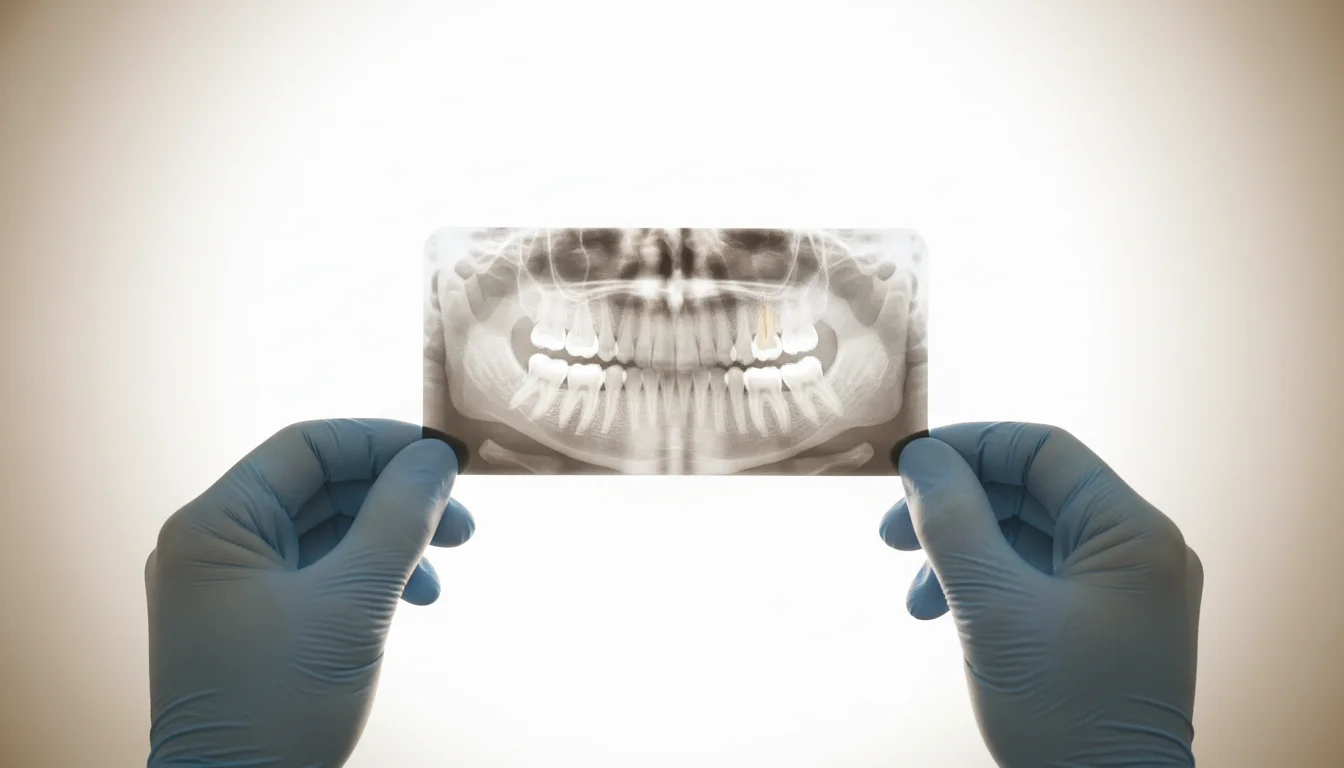

Las radiografías muestran lo que tú no sientes. Por eso se toman.